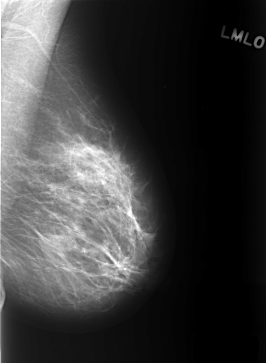

ics_version 1.0 filename C-0402-1 DATE_OF_STUDY 9 1 1996 PATIENT_AGE 49 FILM FILM_TYPE REGULAR DENSITY 2 DATE_DIGITIZED 15 10 1998 DIGITIZER LUMISYS LASER SEQUENCE LEFT_CC LINES 5552 PIXELS_PER_LINE 4056 BITS_PER_PIXEL 12 RESOLUTION 50 NON_OVERLAY LEFT_MLO LINES 5440 PIXELS_PER_LINE 3984 BITS_PER_PIXEL 12 RESOLUTION 50 NON_OVERLAY RIGHT_CC LINES 5640 PIXELS_PER_LINE 3800 BITS_PER_PIXEL 12 RESOLUTION 50 OVERLAY RIGHT_MLO LINES 5448 PIXELS_PER_LINE 4000 BITS_PER_PIXEL 12 RESOLUTION 50 OVERLAY |